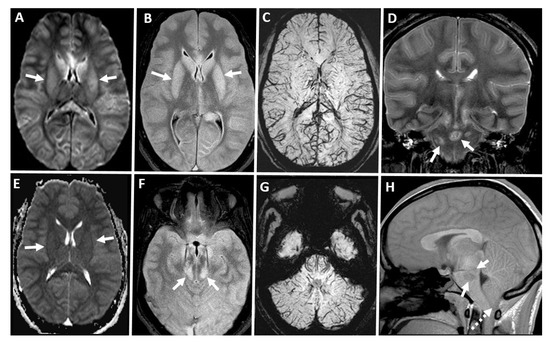

7.7. Magnetic Resonance Imaging (MRI) Brain

7.8. Magnetic Resonance Angiography (MRA) Brain

7.9. Magnetic Resonance Perfusion (MR Perfusion) Brain